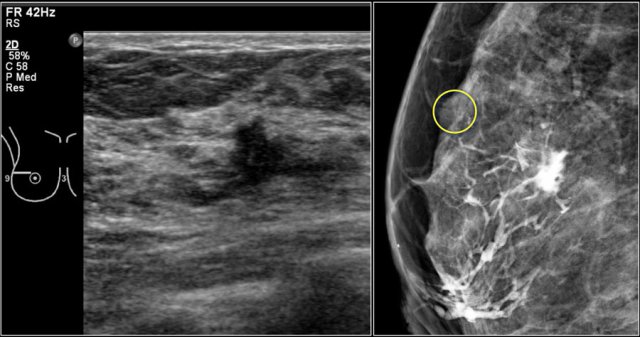

Notice the distortion of the normal breast architecture on oblique view (yellow circle) and magnification view.

A resection was performed and only scar tissue was found in the specimen.